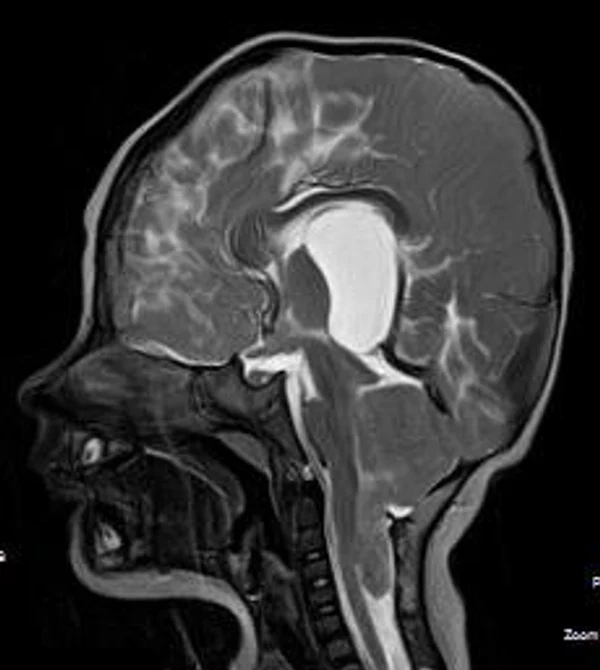

кисты, аномалии Денди-Уокера и др.Операции при внутричерепных кистах. В основном встречаются арахноидальные кисты различных локализаций и кисты сосудистых сплетений боковых желудочков. Пациентам с врождёнными кистами операции проводятся в следующих ситуациях: увеличении объема кисты в динамике, наличии клинических проявлений, компрессии и дислокации мозговых структур, наличии окклюзии ликворных путей. Нами используются 2 способа хирургического лечения кист: эндоскопическая перфорация стенок кист и открытая резекция кист. Открытая резекция кист проводится при ретроцеребеллярных арахноидальных кистах (рис. 2), при арахноидальных кистах межполушарной щели при отсутствии непосредственного контакта их стенок со стенками расширенных желудочков головного мозга и повторного увеличения кист средней черепной ямки после эндоскопической кисто-цистерностомии. Техника операции заключается в проведение краниотомии и максимальном иссечении стенок кист с созданием широкого сообщения кист с субарахноидальным пространством. Эндоскопические операции проводятся при арахноидальных кистах межножковой и пинеальной цистерн, арахноидальных кистах межполушарной щели при тесном контакте их стенок со стенками расширенной желудочковой системы (рис. 3), первично при арахноидальных кистах средней черепной ямки, а также при кистах сосудистых сплетений боковых желудочков. При арахноидальных кистах межножковой цистерны эндоскопически проводится перфорация стенок кисты, сообщая ее с просветом III желудочка и межножковой цистерной – эндоскопическая вентрикуло-кисто-цистерностомия (рис. 4). При арахноидальных кистах пинеальной цистерны проводится перфорация кисты в передне-верхних её отделах с созданием сообщения полости кисты с просветом III желудочка – эндоскопическая кисто-вентрикулостомия. С целью предотвращения облитерации сформированного отверстия иногда в полость кисты под контролем эндоскопа вводится стент перфорированный на протяжении (рис. 5, 6). Эндоскопическая кисто-цистерностомия выполняется при арахноидальных кистах средней черепной ямки. При этом создается широкое сообщение кисты с базальными цистернами. При кистах сосудистых сплетений боковых желудочков проводится их вскрытие в просвет боковых желудочков – эндоскопическая кисто-вентрикулостомия. При множественных кистах проводится их хирургическое сообщение между собой – интеркистосмия